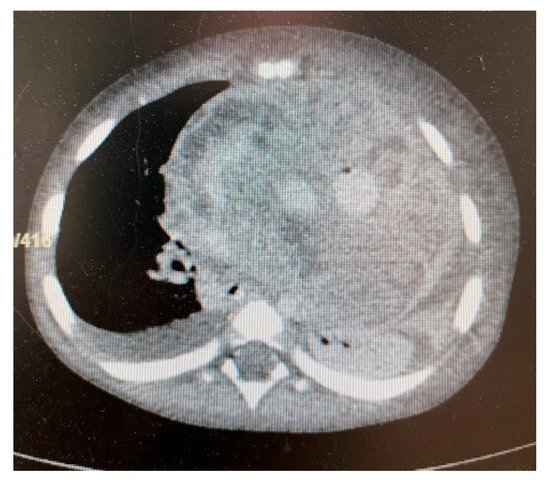

3. Results